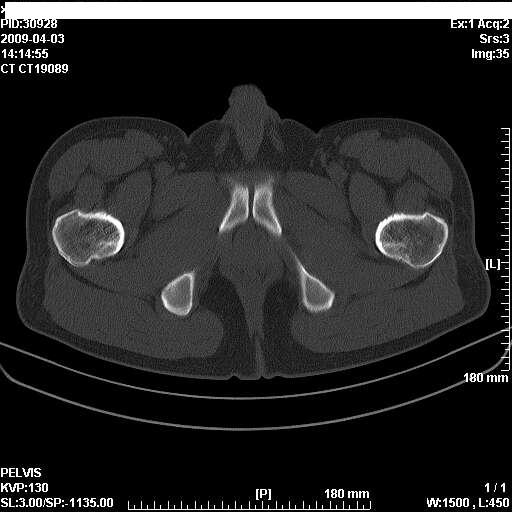

以下是引用随光逐影在2009-4-4 15:13:00的发言:[br]考虑双侧股骨头无菌性坏死;建议行mri检查进一步明确诊断。

以下是引用余辉在2009-4-4 14:22:00的发言:[br]双侧髋关节诸构成骨未见明显异常.必要时mr检查[br]患者症状已有两年,可能要同时从其他方面找原因,个人觉得不排除双侧骶髂关节有问题,建议ct检查